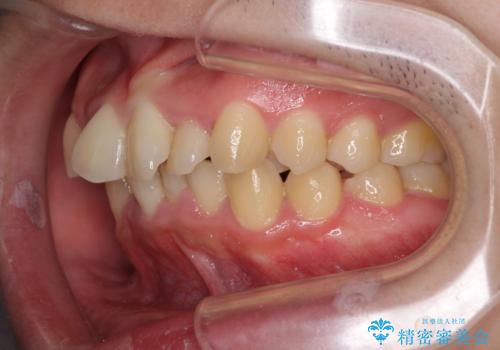

強い咬み込みですり減った前歯 デコボコを抜歯矯正で整える

口元の突出感はないものの、上顎前歯のデコボコが著しかったため、上顎左右第一小臼歯2本を抜歯することとしました。

咬合力が非常に強く、抜歯したスペースがなかなか閉じないであろうことは予想できましたが、思っていた以上に期間がかかりました。

前歯のすり減りも著しかったため、仕上げの位置の調整にも期間を要しました。